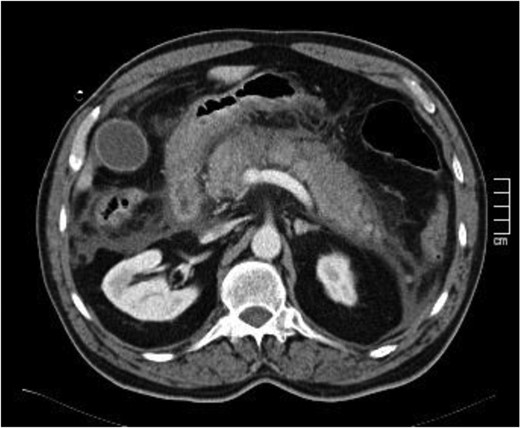

The case report refers to a 62-year-old man with medical history of hypertension, dyslipidemia and previous coronary stent placement. He went to the emergency department with upper abdominal pain with few hours of onset and vomits. The initial serum amylase was 2306 U/L and urinary amylase was 14 231 U/L. He met only one Ranson criteria at admission (Table 1). The first CT showed signs of a non-complicated acute pancreatitis (Fig. 1). He remained under surveillance and suffered clinical deterioration with progressive abdominal pain and tenderness and for this reason he was admitted on the intensive care unit (with an APACHE II score at admission of 15) where he progressed rapidly to multiple organ failure in <24 h. Due to this sudden worsening, with suspicion of a bowel perforation, a new CT scan was performed, showing significant gas dissection through the fascial planes with pneumoperitoneum and pneumoretroperitoneum (Fig. 2), however, without extraluminal contrast leakage evidence. This radiological gaseous pattern could not exclude a visceral perforation and raised the possibility of an anaerobe gas-producing bacteria presence. This sudden and progressive clinical deterioration together with an uncertain perforation or even an infected pancreatitis requiring for drainage motivated the beginning of empiric antibiotherapy with Meropenem and Metronidazol and an exploratory laparotomy on the operating room.